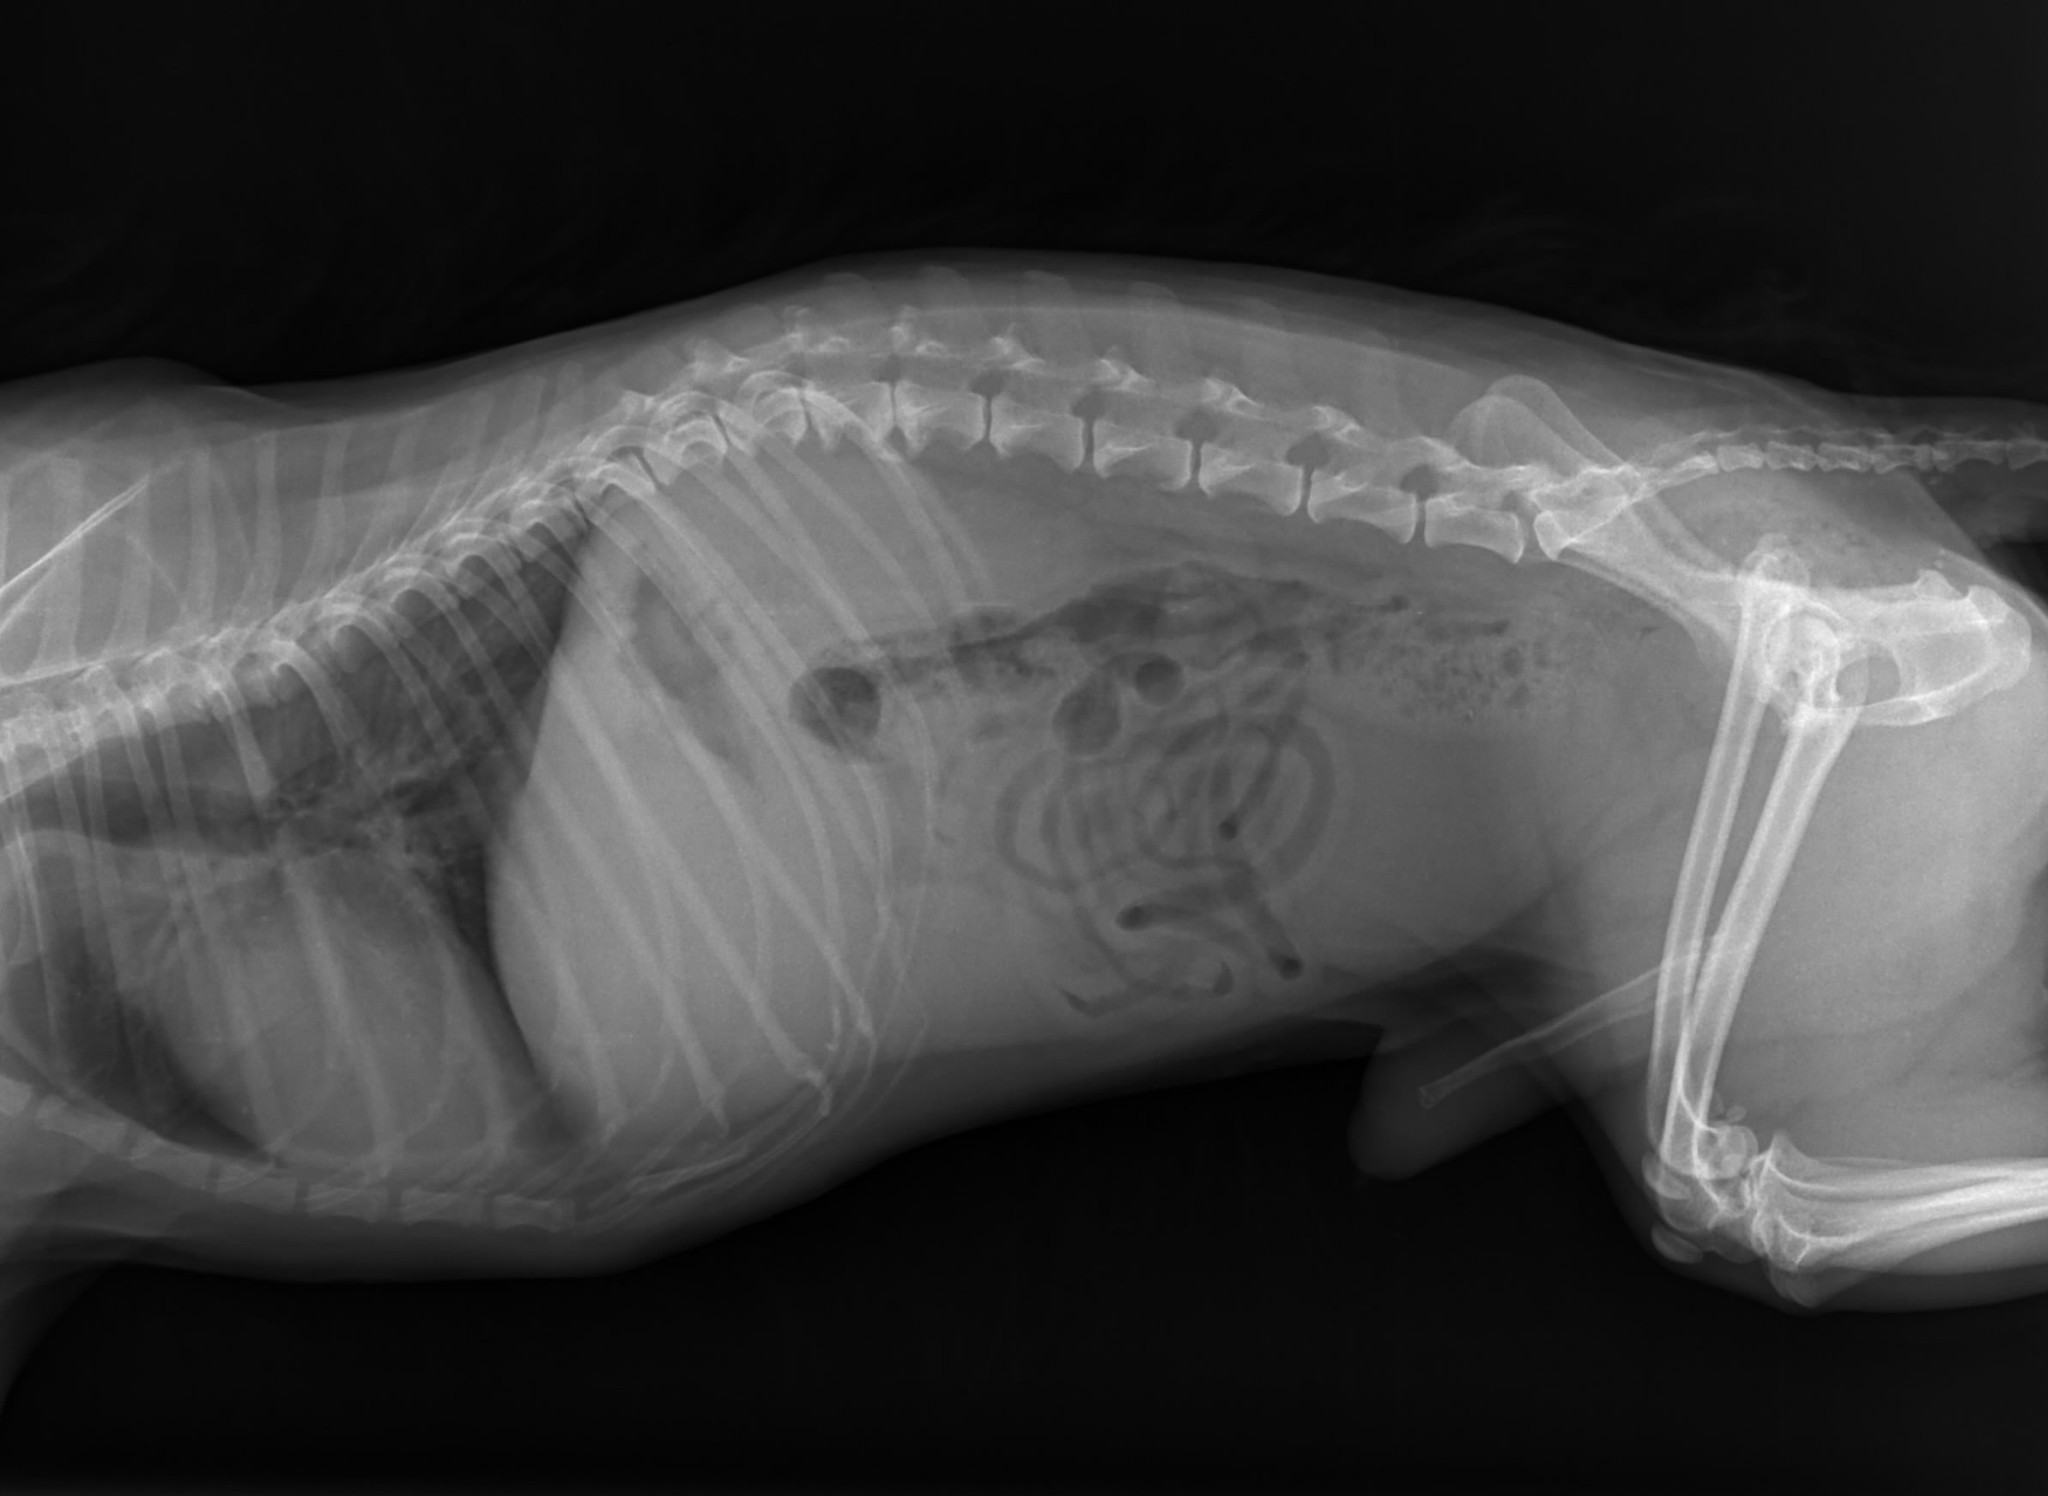

Właściciel od samego początku jasno powiedział, że nie dołoży ani złotówki do leczenia. Gdy usłyszał diagnozę — skomplikowane złamanie łapy, złamanie miednicy i liczne obrażenia — zażądał uśpienia psa.

W sobotę natychmiast zawieźliśmy Dżakusia do kliniki w Bohuminie. Otrzymał tam fachową pomoc, pełną diagnostykę, kroplówki i całodobową opiekę szpitalną. Niestety jego stan był znacznie gorszy, niż przypuszczaliśmy.

Dodatkowo wykryto anaplazmozę, poważne problemy z krwią oraz dramatycznie złe wyniki morfologii i biochemii. Aby mógł zostać zoperowany, konieczna była pilna transfuzja krwi. Po krew musieliśmy jechać aż do Katowic. Koszt samej krwi wyniósł 900 zł.

Przed Dżakusiem kilka operacji. Każda trudna, długa i bardzo obciążająca dla jego wyniszczonego ciała. Leczenie prowadzone jest etapami tylko po to, by miał szansę to wszystko przeżyć.